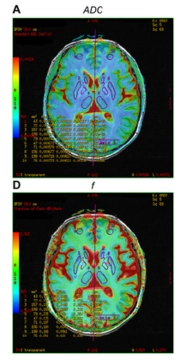

Ultrasonic Cardiac Output Monitor (USCOM) Parameters in Pediatric COVID-19 Patients: A Case Series

Maryam VafapourORCID,

Ramin Zare MahmoudabadiORCID,

Mohammad RadgoudarziORCID,

Amir GhadipashaORCID*,

Majid KarubiORCID,

Ali Manafi AnariORCID

,et al.

|

Final Published